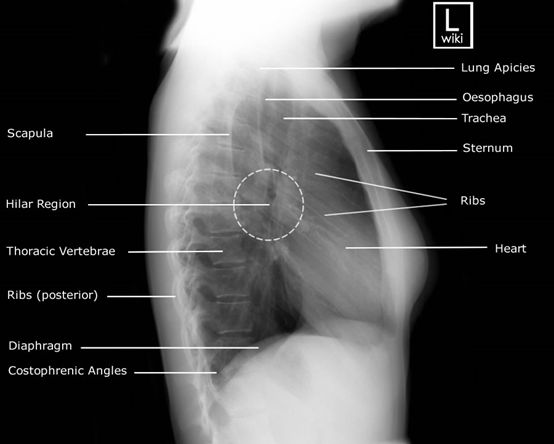

8.有關胸椎側位X光素片攝影,下列何者最正確?

(A)使用呼吸技術(breathing technique)模糊覆蓋在胸椎骨上面不需要的肋骨及肺臟紋路

(D)深吸氣後停止呼吸